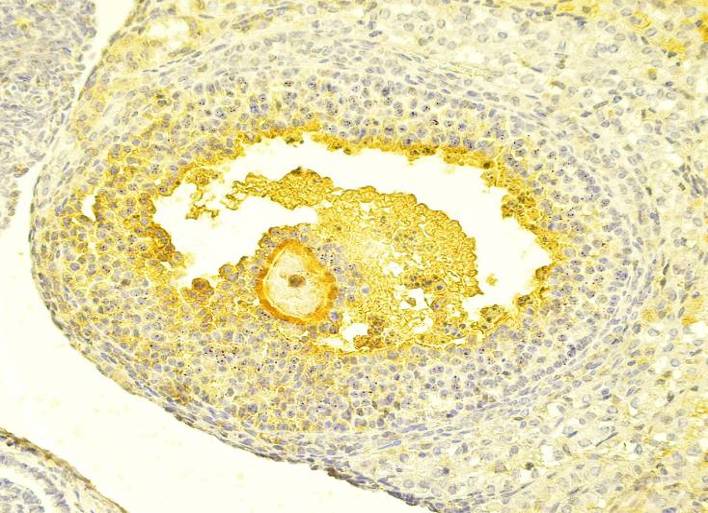

3. After ten days Adriamycin drug injection, with continued oral administration, dosing preventive dose (H+A-III), Graafian follicles showed a clear decline concerning the degradation as compared with the time II (H+A-II). In addition, there was an increase in the number of semi-natural Graafian follicles in early stages. Nevertheless, the morphology of Graafian follicles in the early stage in this group has a perfectly similar arrangement to the complete Graafian follicles, with the presence of some traces of decomposition, such as a little spread in the Granulosa cells within the antrum, and spaces in the thin Theca folliculi. However, the Oocyte are semi-normal and its central nuclei are central (in spite of its terminal existence at some of the Oocytes in the Graafian follicles). This is in addition to the presence of fatty gaps, and partial shrinkage in its cytoplasm (fig. 15). As for the divisive ability of the Granulosa cells, there was a clear improvement as compared with the first and second-time (H+AI) (H+A-II) (fig. 16).

Fig. 15: transverse section in youthful Graafian follicles in females injected with the drug and administrated with the preventive dose (the third time (H+A-III)-(H & Ix400) Fig. 16: Transverse section in youthful Graafian follicles in females injected with the drug and administrated with the preventive dose (the third time (H+A-III)-(Ki67x400)